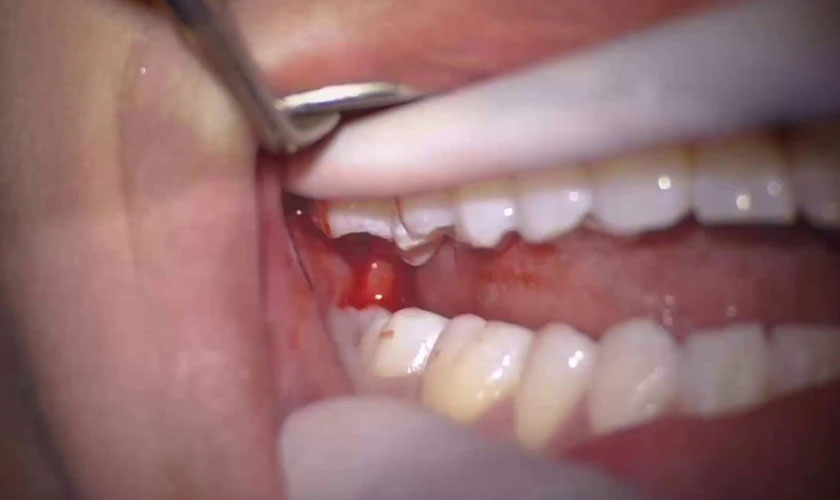

Răng khôn mọc khi nướu đã khá cứng, chính vì vậy khi nhú lên sẽ phá vỡ các liên kết của nướu, khiến nướu sưng phồng và tấy đỏ. Vì nướu là bao bọc toàn bộ răng nên khi răng nhú lên càng nhiều thì nướu càng sưng to, đến khi bạn có thể sờ hoặc nhìn thấy được cũng là lúc nướu bị tổn thương nhiều nhất.

Răng khôn hàm trên khi mọc có thể gây sưng đỏ nướu

Và khi răng đã mọc ổn định và định hình được chiều mọc, nướu sẽ trở về trạng thái bình thường. Ngoài ra, khi nướu sưng đau, các bạn cũng sẽ cảm nhận được vận động hàm có phần chậm chạp và nặng nề hơn bình thường.